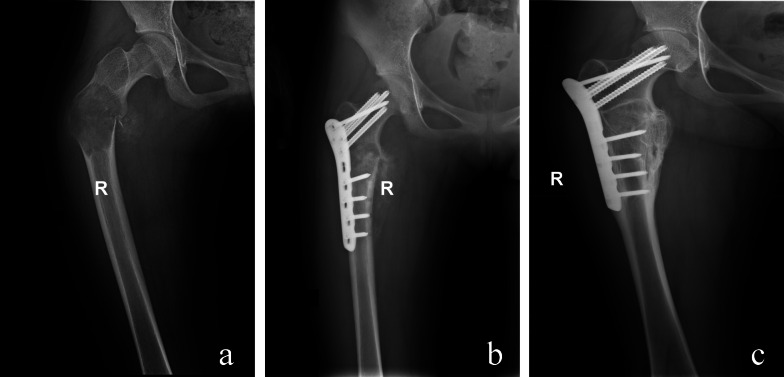

Materials and methods: This retrospective analysis included 28 patients (30 extremity) with severe pain, pathological fractures, angular deformities, or extensive cortical bone involvement. On the basis of the surgical approach, patients were divided into four groups: group 1, curettage, allograft, and plate fixation for six patients (six extremity); group 2, elastic stable intramedullary nailing fixation for six patients (six extremity); group 3, Fassier-Duval telescopic system fixation for eight patients (nine extremity); and group 4, interlocking intramedullary nail for eight patients (nine extremity).

Results: All patients achieved bony union and pain alleviation with no recurrence of deformities. The refracture rate during the follow-up was zero cases (0%; group 1) versus one (16.7%; group 2) versus zero (0%; group 3) versus zero cases (0% group 4) (p > 0.05). Instances of internal fixation loosening were zero cases (0%; group 1) versus zero (0%; group 2) versus five (55.6%; group 3) versus zero cases (0%; group 4) (p < 0.05). The musculoskeletal tumor society (MSTS) scores of the four groups were 27.5 (group 1) versus 27.7 (group 2) versus 26.3 (group 3) versus 28.7 (group 4) (p < 0.05).